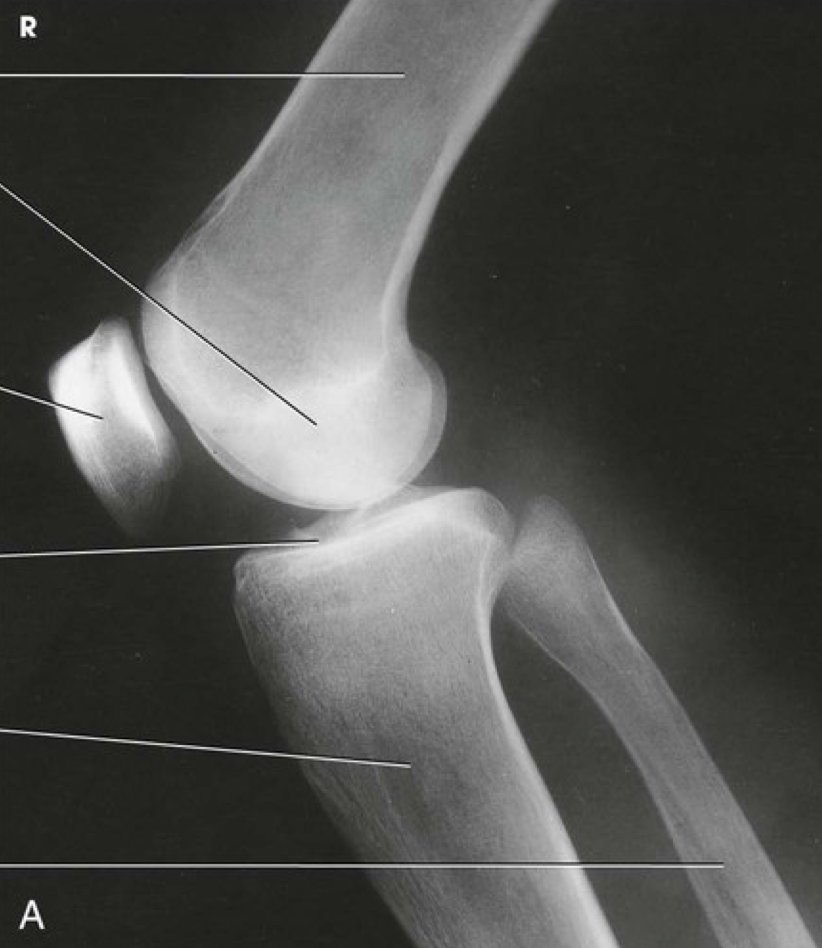

Question 3

Question

Label the image

Image:

0e626c3f-6a7b-47c6-b350-8e3068a35b04 (image/png)

Answer

femur

patella

lateral epicondyle

lateral condyle

lateral tibial plateau

intercondylar eminence

head of fibula

tibia

fibula